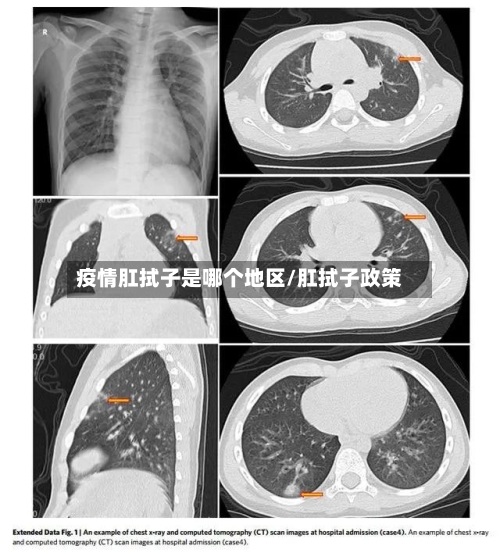

而在进行肛拭子检测的时候,是基于这样的一个现象 ,那就是从粪便当中排毒是冠状病毒感染过程当中的一个比较常见的现象。也就是说一般来说粪便检测阳性的持续时间可能会比咽式子更长一些,也就更有利于我们早一点对已经感染的病人的筛查准确率,会相对的提高一些。

近来为尽早发现无症状感染者,一些地方增加了肛拭子核酸检测 。但此举能否实现提高检出率的目的 ,仍需进一步的科学支撑。在1月22日举行的北京新冠防控新闻发布会上,相关负责人介绍,对大兴区新增感染病例所在区域人员全部进行了鼻咽拭子、口咽拭子、肛拭子及血清检测。

〖肆〗、新增肛拭子采样的背景:自实施“双阴性”“阴性 ”报告登机规定以来,仍有境外输入确诊病例 ,“阴性”乘客落地后测出阳性的情况屡见不鲜。为进一步加强检测,严防漏网之毒,中国部分地区近日开始对隔离点等重点人群的新冠核酸检测新增肛拭子采样。